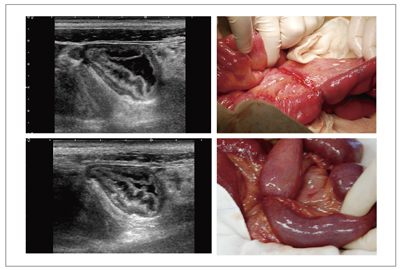

図9は,腹部膨満感,下腹部痛で来院した70歳代,男性の回盲部CT画像とのSmart Fusionである。CTでは腫瘤の存在や炎症像の確認はできるが,内部の構造は不明瞭である。超音波では,腫瘍内部の重積様変化が明瞭にとらえられた。高度に肥厚した腸管壁のエコーレベルは,均一な低エコーを呈していた。周囲には,炎症を反映した強いisolation signが見られた。また,一塊となった腫瘤は大きく,CT画像が回腸末端から連続する腫瘤像を的確にとらえ,エコー像をナビゲーションし情報を得た。Smart Fusionの活用により小腸リンパ腫(回腸末端部)が回盲部から盲腸へ隆起し,回腸・結腸型の腸重積様に一体化した腫瘤を形成した病態と診断できた。緊急手術が施行され,術前診断と一致した手術所見であった。

図9 70歳代,男性,悪性リンパ腫の小腸病変に施行したSmart Fusion画像